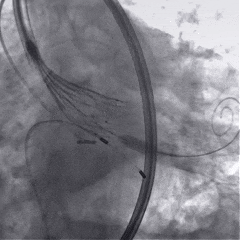

术中影像

根部造影

球囊预扩

瓣膜稳定释放

瓣膜展开后造影

再次造影,确认瓣膜位置

脱钩后造影,瓣膜位置可,几乎无瓣周漏